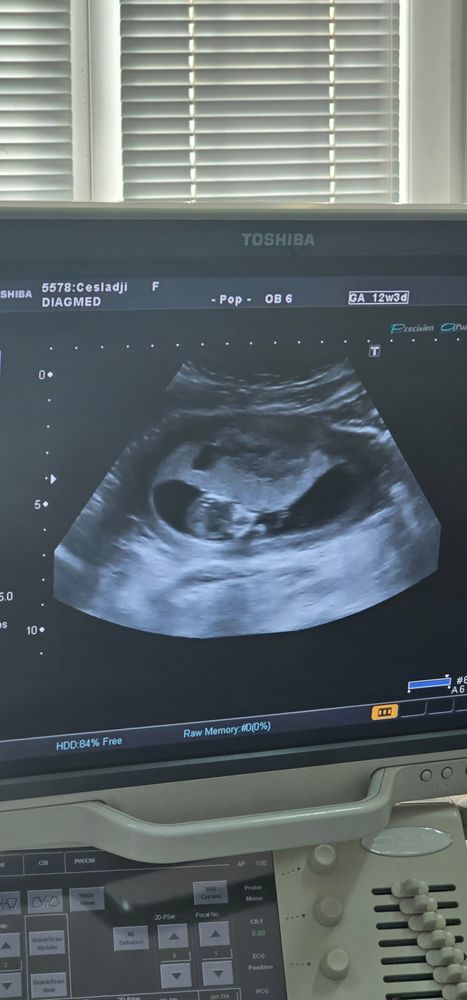

Результаты УЗИВсем привет. Тянул живот 2 дня сходила на узи сегодня. Срок 12 недель 3 дня.

В итоге обнаружили тонус матки .

В плаценте киста 14 мл .

Плюс плодное яйцо из за тонуса поменяло форму. Поставили угрозу